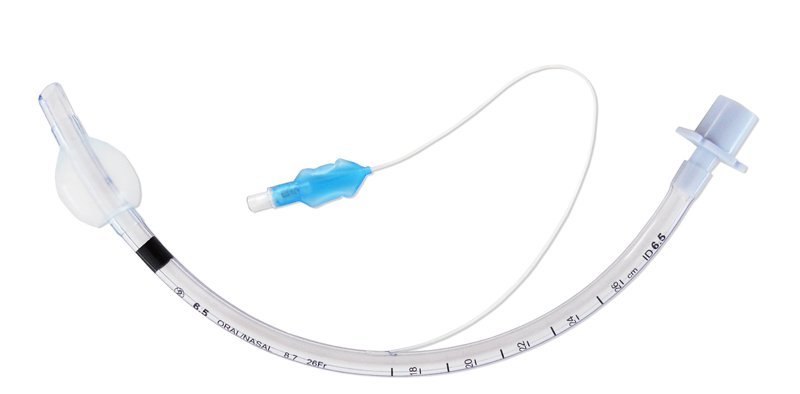

Endotracheal Tube (Cuffed)

Endotracheal Tube (Cuffed)Our ProductsFrom SurgicaveUplode:9 months ago from India